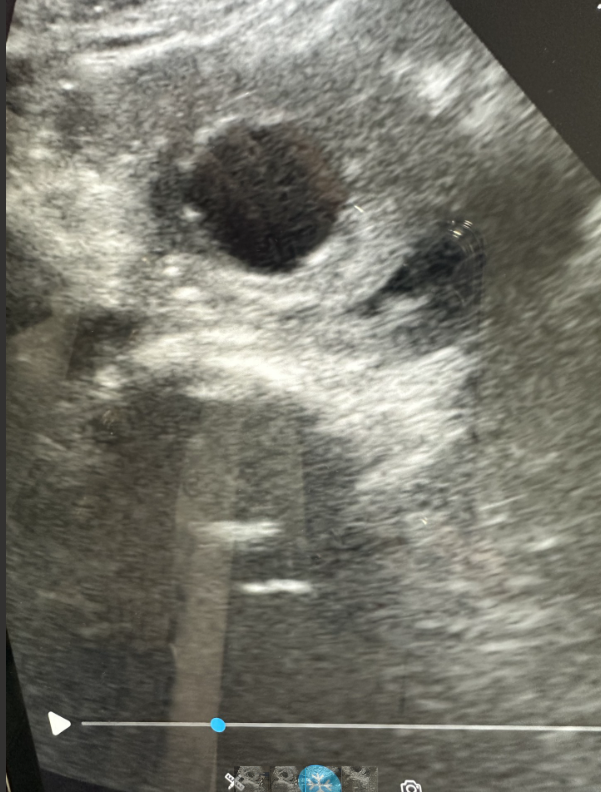

La ecografía clínica realizada en nuestra consulta de Atención Primaria mostró un aneurisma de aorta infrarrenal de 5,3 × 8,1 cm, con trombo intramural y sospecha de disección, hallazgo no presente en estudios previos.

Sospecha de complicación de aneurisma abdominal (disección/parcial rotura contenida).